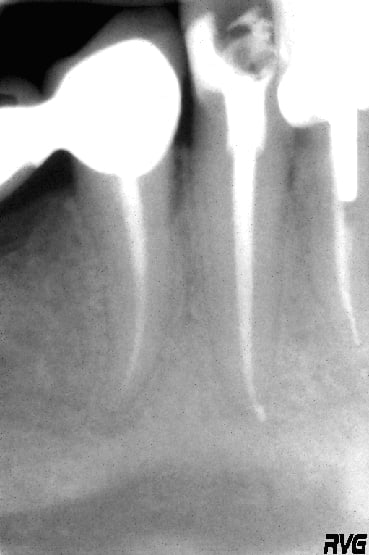

J'ai appliqué la methode "olé olé" de stéphane.

En ce qui concerne l'IRS, c'était même pas la peine d'y penser car le Protaper F2, à sa base, a un diamètre trop important.

1. J'ai commandé (à l'unité) un trépan de la trousse de masseran correspondant en interne au diamètre du F2 ainsi qu'à celui qu'un embout de "Glyde" pour le diamètre externe.

2. J'ai dégagé la partie haute de linstrument fracturé (Fraise, US et trépan)

3. Avec de la résine autopo luxatemp pour provisoires j'ai rempli l'embout du glyde que j'ai positionné sur l'instrument.

4. 3 min plus tard, il n'y avait plus qu'à dévisser et le tour était joué.